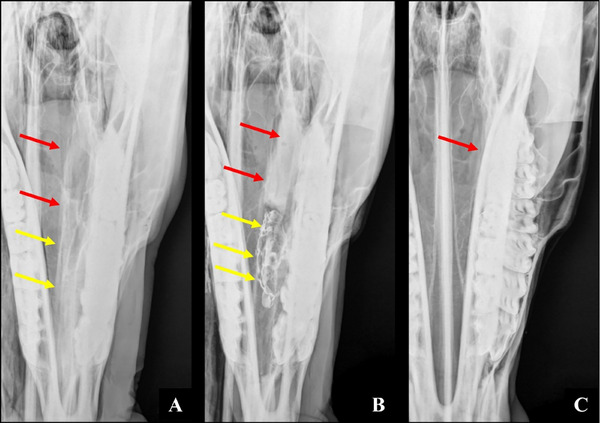

Radiographic examination of the skull is a well-established and indispensable procedure for the diagnostic evaluation of dental and paranasal sinus disorders in horses. Complementary projections make significant contributions to radiographic diagnosis in nasal conchae disorders. This article describes a complementary radiographic projection designed for the evaluation of the conchal sinuses and bullae in horses. Six equine cadaveric heads were used. Specimens were dissected, and openings were created in the ventral and dorsal nasal conchae for the introduction of radiopaque material. The new radiographic projection was named lateral 75° dorsal-lateral ventral oblique view. This projection was obtained with the mandibular rami resting on the imaging plate and the mandible displaced toward the side of interest (partial excursion). The X-ray beam was directed dorsoventrally, slightly angled toward the side of interest (left or right offset mandible dorsoventral view), and centered at an imaginary line connecting the tips of the facial crests. The lateral 75° dorsal-lateral ventral oblique view provided enhanced visualization and allowed correct identification of equine conchal structures. Lateral displacement of the mandible and the 75° angle of inclination to the vertical plane eliminated the superimposition of anatomical structures, facilitating radiographic image interpretation and increasing diagnostic accuracy. This complementary projection is recommended in all cases of sinonasal disorders in horses.